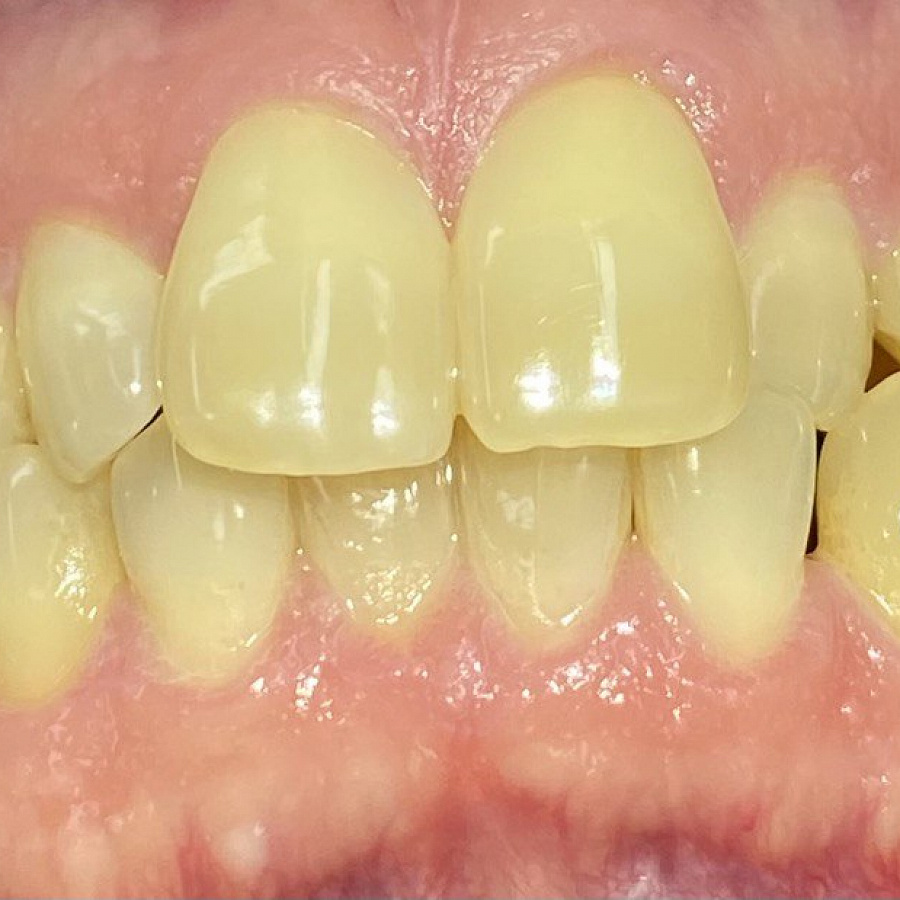

- восстановление плотных межзубных контактов с помощью ортопедических конструкций

- виниры 12, 22 для удлинения резцов.

Ортодонтическое лечение с помощью элайнеров длилось 10 месяцев. Далее последовало протезирование и установка виниров.